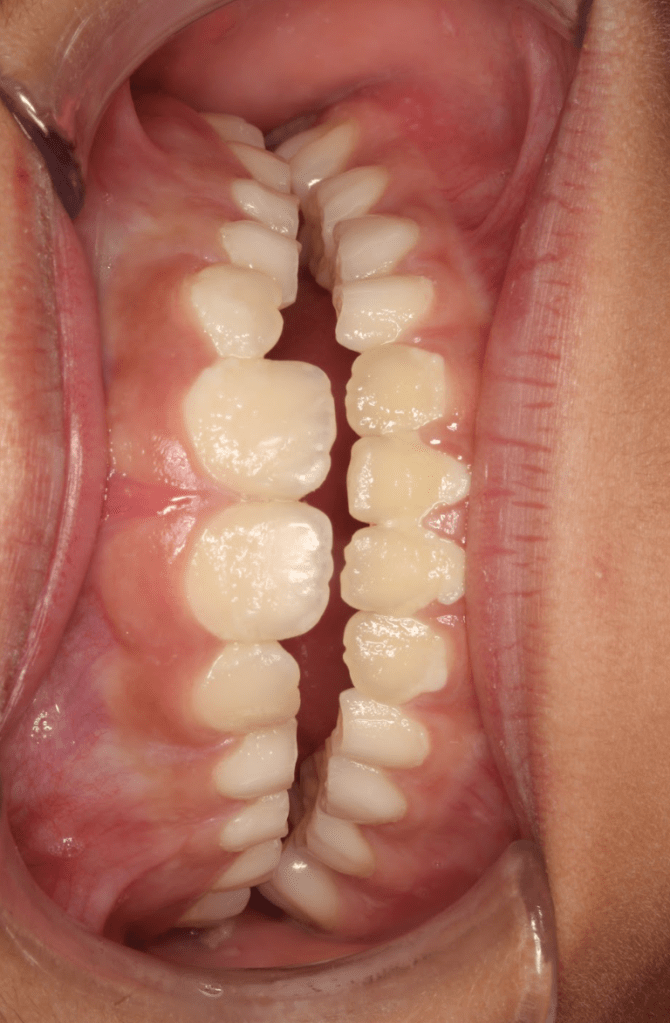

Endodoncia diente temporal, ausencia definitivo